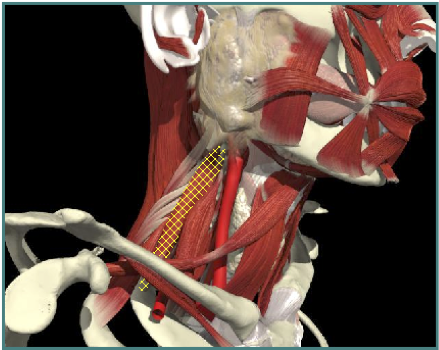

ACCURACY OF LOCALIZATION - SCALENES

ACCURACY OF LOCALIZATION LEVATOR SCAPULAE

LOCALIZATION OF MUSCLES IN DEEPER LAYERS

- Muscles deep

- Not easily identified by surface landmarks

- Not palpable on examination

INJECTION SITES